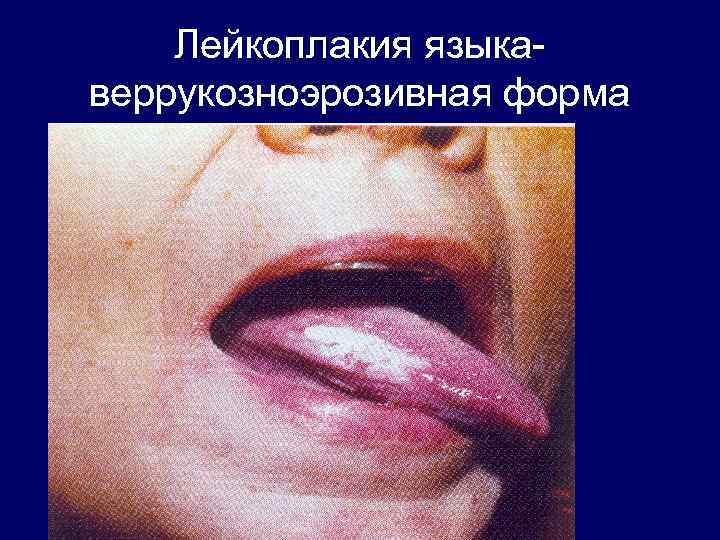

Лейкоплакия языкаверрукозноэрозивная форма

Лейкоплакия языкаверрукозноэрозивная форма